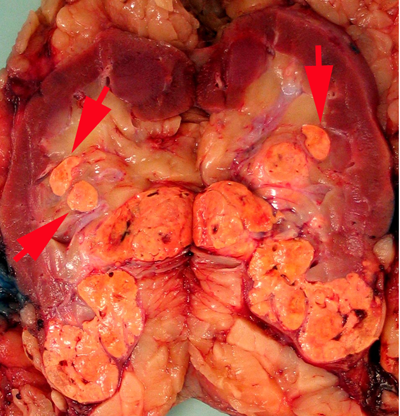

Renal sinus invasion

In the renal sinus, large veins are thought to become involved before small veins and as such small vein involvement usually implies large vein involvement. The renal sinus has rich venous anastomoses, therefore any venous involvement is likely to have metastatic risk. The majority of participants in the pre-meeting survey agreed that contact with renal sinus fat, (Fig. 2A) or loose connective tissue, clearly beyond the renal parenchyma indicated renal sinus invasion. Large sinus veins, including segmental branches of renal vein have marked variability in amount of smooth muscle and it was agreed that, if there are any endothelial lined spaces containing tumor within the renal sinus, regardless of size, this must also be considered renal sinus invasion (pT3a) (Fig. 2B).

Figure 2A  Figure 2B

Figure 2. A, Carcinoma in contact with renal sinus fat indicates renal sinus invasion; B, Carcinoma within vascular channels within the renal sinus, regardless of size is also considered renal sinus invasion.